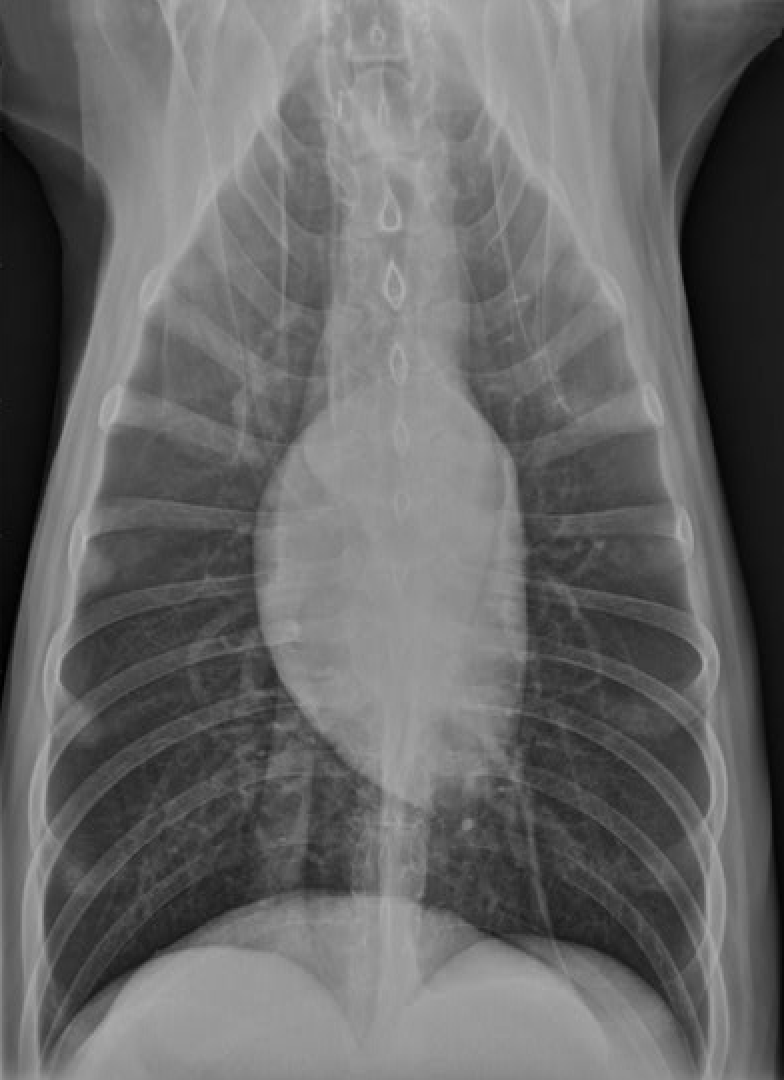

Where is the apex of the heart?

towards the left of the midline

why does the heart appear to sit to the left of the midline in this dorsal ventral radiograph

Because of the size of the right lung

Which chamber of the heart gives rise to the ‘apex’ of the heart?

left ventricle